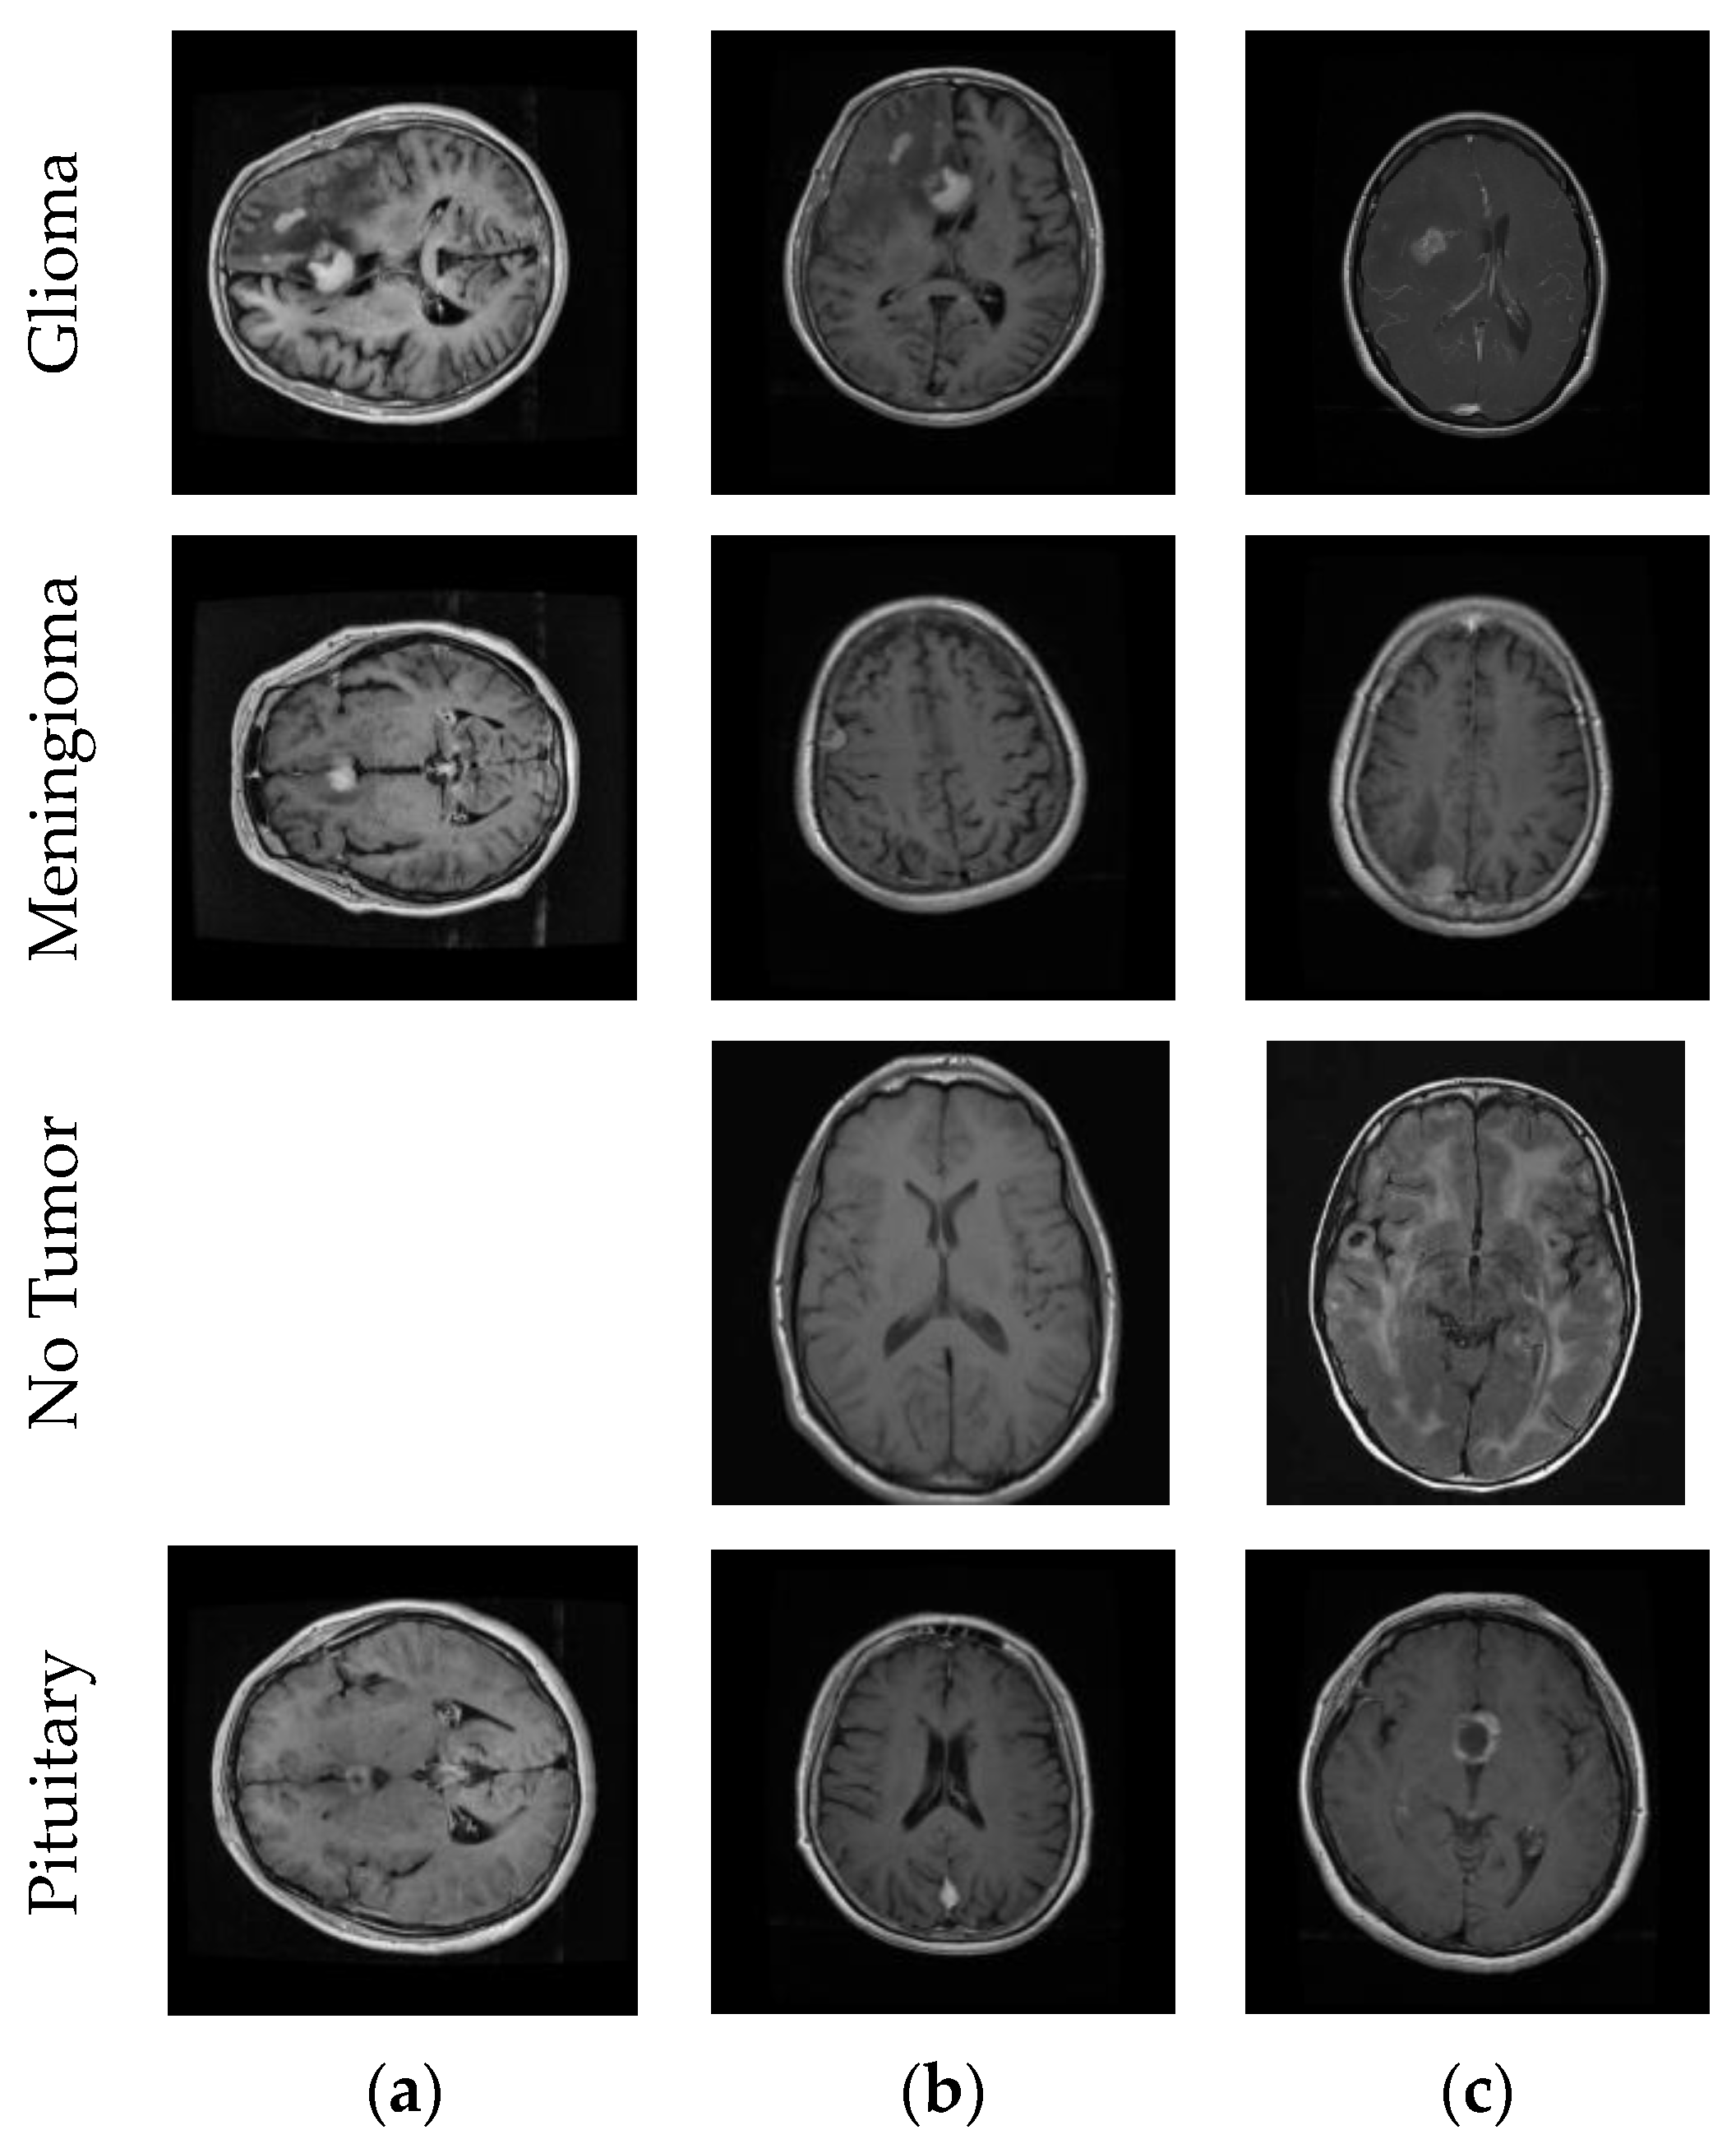

This study leveraged three datasets for its research purposes. To begin with, dataset 1 [56] is a publicly accessible Figshare brain tumor dataset containing a total of 3064 brain MRIs. This dataset has three distinct classes: glioma, meningioma, and pituitary tumors. Specifically, this dataset comprises 1426 glioma images, 708 meningioma images, and 930 pituitary tumor images. Moving to dataset 2 [57], it is composed of four classes: glioma (926 images), meningioma (937 images), pituitary tumors (901 images), and a category denoting the absence of tumors (500 images). Finally, dataset 3 [58] is also an open-source brain tumor dataset that merges data from three sources: Figshare [56], SARTAJ [57], and Br35H [59], resulting in a total of 7023 brain MRIs. This dataset represents four categories: healthy brain images, meningioma, pituitary, and glioma tumors. Concretely, there are 2000 images of healthy individuals, 1621 glioma images, 1645 meningioma images, and 1757 of pituitary tumors. Figure 1 shows example MR images from the datasets.

Figure 1.

Sample MR images from the datasets. (a) Dataset 1; (b) Dataset 2; (c) Dataset 3.